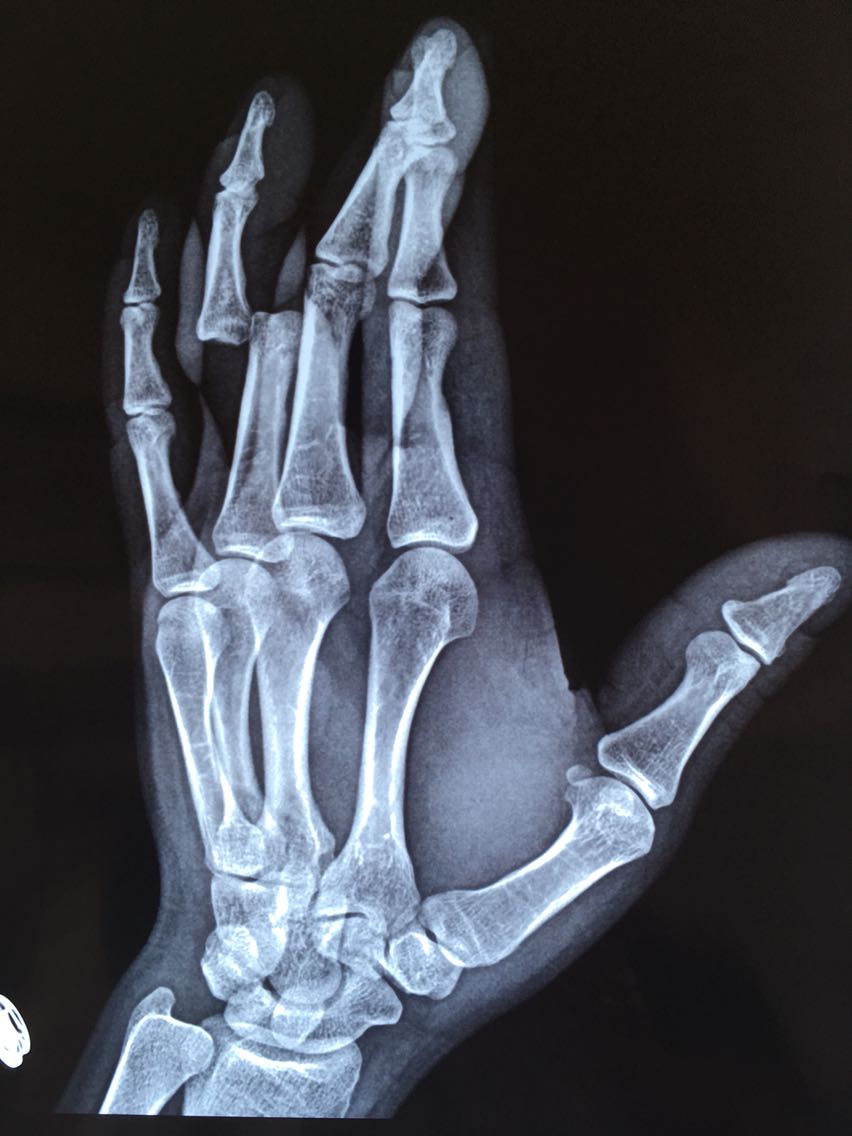

主诉:左手环指外伤后畸形伴功能障碍1小时余。 病史:患者M/30,1小时前与他人发生争执被他人扭伤左手环指,出现疼痛、畸形伴功能障碍。

查体:左手指体肿胀,近指间关节以远指体尺偏畸形,近指间关节体表触压痛阳性,近指间关节尺侧侧方应力试验阴性,桡侧侧方应力试验阳性,被动伸指成过伸样改变。

诊断:左手环指近指间关节脱位并关节囊、侧副韧带、掌板断裂 治疗:切开桡侧副韧带、关节囊缝合修复术及掌板止点金属骨锚钉重建修复术